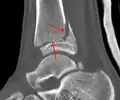

A triplane fracture of the ankle as seen on plain X-ray

A triplane fracture of the ankle as seen on CT

CT

CT scans may be indicated when there is concern for a highly comminuted fracture or a fracture involving the joint surface.[9] This imaging may be used for surgical planning.

- Triplane fractures are a special type of fracture that involves the immature skeleton. It has a coronal plane in the metaphysis, an axial plane in the physis, and a sagittal plane in the epiphysis.[14]